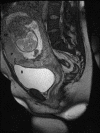

Fig. 4.

Sagittal T2-weighted MR images. The upper wall of the bladder (B) is locally deformed from the left to 35 mm in length, contact and pressing (arrow) from the side of the placenta (P) is visible, in some places the wall contour of the bladder of the normal signal is clearly differentiated and hypervascular, inadequate myometrium (M)